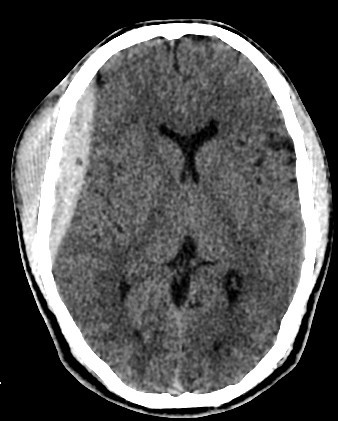

• A well-defined extraxial elliptical shape fresh blood density seen in the right fronto-parietal region.

• The lesion exert little mass effect in the form of effacement of the cortical sulci and and mild midline shift.

• right fronto parietal subglial hematoma seen

• Normal size and configuration of the ventricular system.

• No intracerebral or intraventricular recent blood density.

acute extradural hematoma with fracture

• Biconvex (lentiform) hyperdense collection adjacent to the inner table of the skull.

• Mass effect: midline shift, compression of adjacent sulci or ventricles.